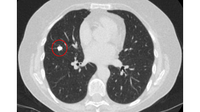

Computed tomography (CT) showing a left upper lobe peripheral nodule with several pleural ‘tags’ and element of retraction of the adjacent pleura. Resection histopathology confirmed a well-differentiated squamous cell lung cancer

From the collection of Dr George Tsaknis, MD, PhD, FRCP(London), MRQA, MAcadMEd, PGCert; used with permission